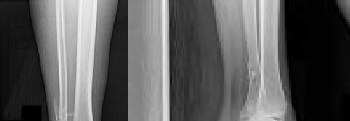

Figure 1 is the radiograph and Figure 2 is the CT image of a 45-year-old woman who fell about 20 feet off her balcony. These images show an isolated, open injury with a 3-cm open medial wound.

The best delayed definitive surgical fixation plan would include

1. lateral plating of the fibula and a percutaneous medial column plate.

2. intramedullary fixation of the fibula and an anterolateral tibial plate.

3. open medial column plating, percutaneous screw fixation of the joint, and lateral fibular plating.

4. screw fixation of the medial column with an anterolateral tibial plate and lateral fibular plating

Discussion: The timely administration of antibiotics has been shown to be the best initial treatment to reduce the incidence of infection following an open fracture. Life threatening injuries must first be addressed. But in this isolated open pilon fracture, antibiotics should be initiated early along with tetanus prophylaxis. Reduction and splinting would stabilize the fracture but these interventions should follow antibiotic coverage. Emergency department irrigation is controversial. Closed reduction and splinting, external fixation, CT scan, and delayed open reduction internal fixation would be the preferred sequence of management. External fixation to provide provisional limb stabilization would be indicated in this length unstable C type injury to provide soft tissue stabilization and prevent further chondral injury. Splinting alone would not prevent shortening and would not allow soft tissue recovery. CT scans prior to limb stabilization are not warranted because the patterns make more sense after the restoration of gross length, rotation and alignment in the external fixator. Initial fibular fixation is also not recommended in this case because the location of incisions could affect the definitive surgical tactic. In this multi-fragmentary fibular injury, anatomic reduction would be challenging and malreduction could occur and influence subsequent reconstructions. Delayed open reduction internal fixation is ideal after the resolution of soft tissue swelling.